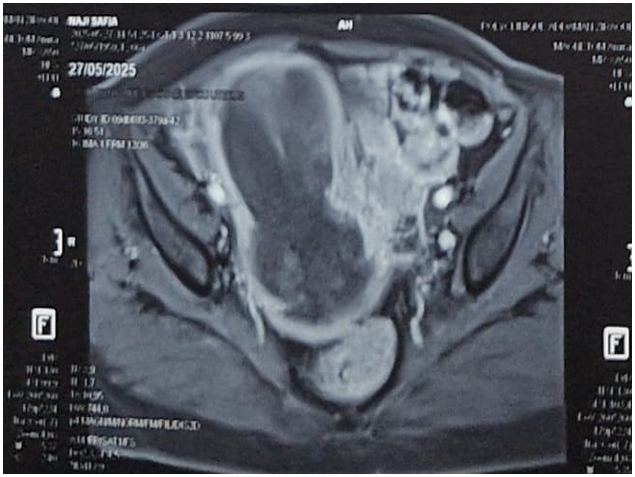

Pelvic MRI:en larged uterus with an endocavitary mass occupying almost the entire uterus, measuring 12x7x6cm. This mass appears to exceed 50% of the thickness of the myometrium, however there is a continuous external band of myometrium that has not been penetrated. At the bottom, it extends beyond the cervix at the level of the anterior wall in the upper third of the vagina. There is no evidence of invasion of the bladder or rectum, with no visible pelvic lymphadenopathy of significant size (Figure 1).

Figure 1: Pelvic MRI image showing an endocavitary uterine mass